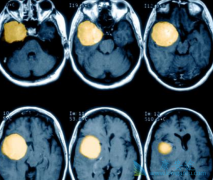

• 肺癌ALK患者病情发生了脑转移后该用克唑替尼还是色瑞替尼?

肺癌ALK患者病情发生了脑转移后该用克唑替尼还是色瑞替尼?

肺癌一直以来就是我国的第一大癌症肿瘤,其中以肺癌EGFR和ALK基因突变最为常见,很多肺癌ALK患者由于治疗不及时,很容易出现肺癌病情的恶化和扩散,其中肺癌脑转移是最为常见的转移形式,那么对于这类肺癌脑转移的患者我们该用什么肺癌ALK药物呢? 克唑 ...